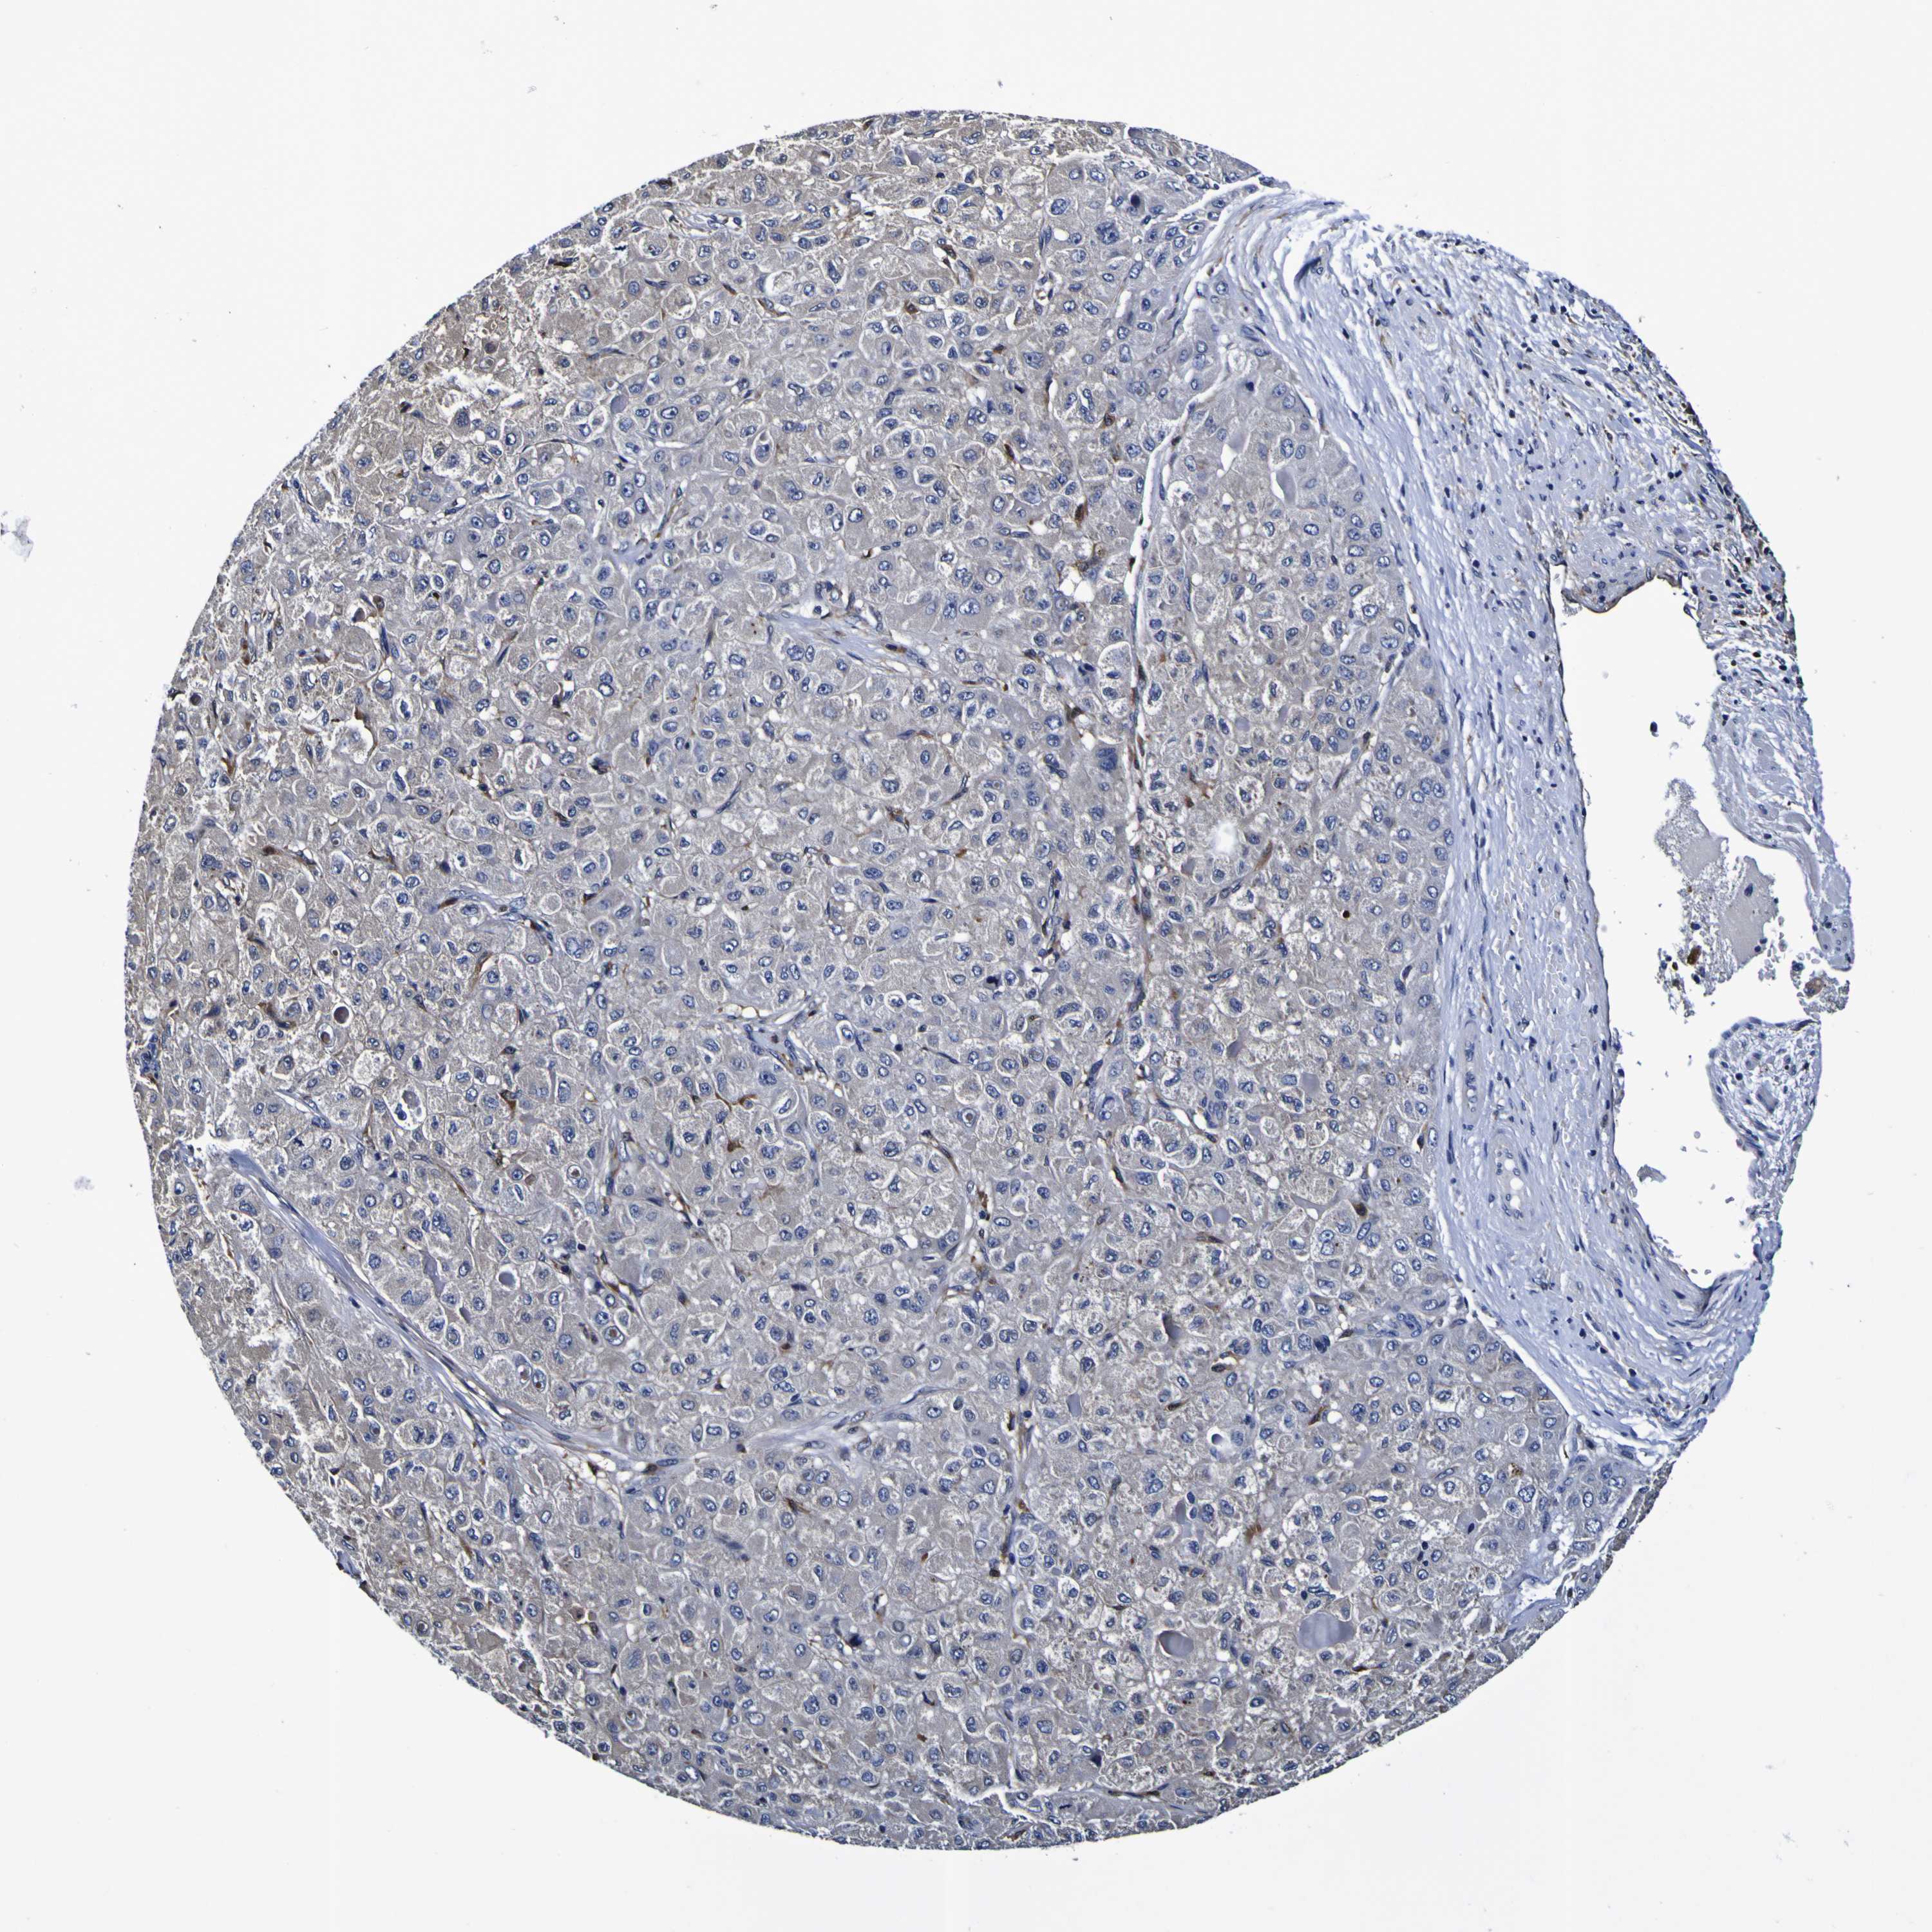

LIVER CANCER - Protein expressioni

A mouse-over function shows sample information and annotation data. Click on an image to view it in a full screen mode. Samples can be filtered based on level of antibody staining by selecting one or several of the following categories: high, medium, low and not detected. The assay and annotation is described here.

Note that samples used for immunohistochemistry by the Human Protein Atlas do not correspond to samples in the TCGA dataset.

Antibody stainingi

Antibody staining in the annotated cell types in the current human tissue is reported as not detected, low, medium, or high, based on conventional immunohistochemistry profiling in selected tissues. This score is based on the combination of the staining intensity and fraction of stained cells.

Each image is clickable and will lead to virtual microscopy that enables deeper exploration of all samples and also displays staining intensity scores, fraction scores and subcellular localization as well as patient and tissue information for each sample.

Antibody HPA044758

Cholangiocarcinoma

Carcinoma, Hepatocellular, NOS